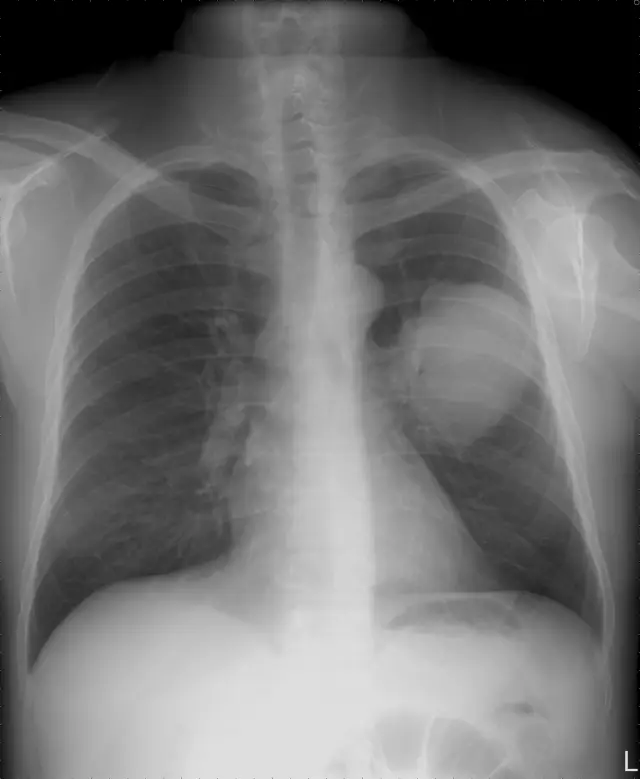

正位胸部X光片(PA)

- 右下肺野可見一圓形致密度增高陰影,邊緣平滑,形態規則,與心臟或橫膈呈分界簽(silhouette)現象不明顯,顯示可能位於肺實質內;非典型的弧形彎月面(meniscus)或楔形模糊,排除大範圍游離積液或次膈下積液。